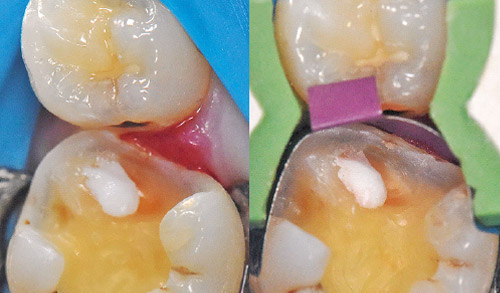

症例は4、5の連続歯修復のビル ドアップ、I.D.S法施術時の状態を掲載する。完全な防湿状態下で、マトリックスバンドがフュージョンウェッジにより歯質に圧接され、マージンとの隙間からラバーダムの色や歯肉、浸出液の漏出が確認されないことがあげられる(図19)。

また連続歯修復ケースでは1歯単位で確実にビルドアップ、I.D.S法を行っていく(図20)。図21はビルドアップとI.D.S法終了時の口腔内写真。

図19 マトリックスバンドと歯肉側マージンに間隙がなく、浸出液、血液が確認されないことが重要。 -

図20 連続歯の症例は1歯ごと確実に施術していく。 -

図21 4 、5のビルドアップ、I.D.S法が完了したところ。隣接面に適度な隙間があることが光学印象をスムーズに行うポイント。